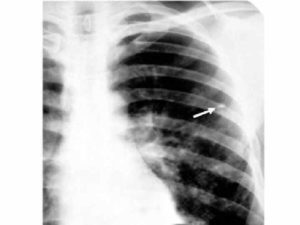

Рентгенологические признаки

Пациенту проводят рентген легких в 2 проекциях. При свежем заболевании на снимке очаги представлены в виде теневых образований небольшого и крупного размера, имеющих округлую форму.

Нередко они локализуются в верхних отделах легких. Для хронической формы патологии характерны плотные фокусы с очагами фиброзных тяжей.

При фиброзе ткани легкого мелкие очаги соединяются и перемещаются к верхушке легкого, а к плевре тянутся тени в виде полос.